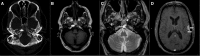

Ecchordosis physaliphora (EP) is a benign notochordal remnant derived from ectopic nests found along the craniospinal axis. It typically presents asymptomatically and is diagnosed using classic radiologic features, particularly location, T1-hypointensity, T2-hyperintensity, and lack of enhancement following gadolinium (Gd) contrast administration. Distinguishing EP from its malignant counterpart, chordoma, is of paramount importance, given the aggressive nature of the latter. Advances in imaging and immunohistochemistry have aided in diagnosis to an extent but, to our knowledge, identification of the genetic fingerprint of EP has yet to take place. Further cytological analysis of these lesions in search of a genetic link is warranted. We propose here a set of diagnostic criteria based on features consistently cited in the literature. In this literature review, 23 case reports were identified and collated into a summary of symptomatic cases of ecchordosis physaliphora. An illustrative case report of two patients was also included.